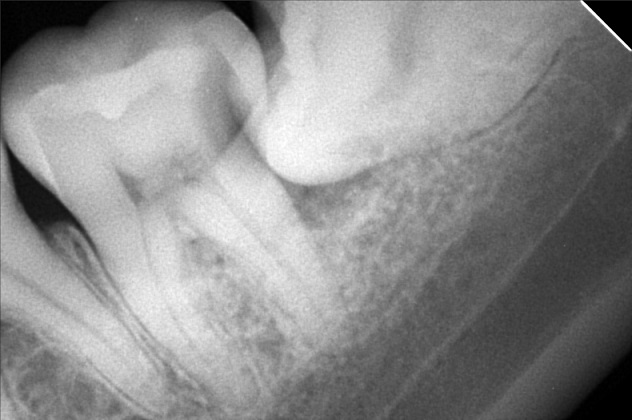

Edit Record Check our patient data records. Add patient information Patient Info Profile picture Last Name First Name Middle Name Birthdate Age Street Barangay City Country Zip Code Contact number Email Procedure 4/8/22- check up ***pano/ ceph ***#46 exo presence of lip tie 04/02/22 odontectomy 48/38- class 3/ mesioverted exo 46/ tongue tie/ ankyglossia frenectomy (laser) pt under IV CS Ozone therapy ****ff up after 2 weeks/ ***for orthodontic treatment 06/16/22 LC 24 OD/ CAOH LC 47 M op/ OZONE 1/11/23- Adj , 16niti Upper, Rotational Wedge # 42D , reattached #35 11/04/22-OP/LC 15,36,26,/mta/XRAY 11/16/22-InsOfBraces/Niti 14/14(MBT0.22) 12/07/22-adj 01/11/23- adj 04/12/23- same wire U/ Lower NiTi 16/ reattached #34,15/IPR between #32-33 05/05/23- U same wire; L SS-16; Resto #14DO, #15MOD, #16D 06/07/23- Informed Consent Resto #14DO (redo) Ortho UL same wire Remove RW #33 Monkey elastics #13-#23-#33-#43 07/19/23- Lc 36 occusal, lingual 18 ss U 18ss l rw 33 distal 08/18/23- 09/15/23- same wire #22 extrude 10/13/23 - adjustment, same wire - RW on #12 mesial 12/13/23-16X16 L -Penguin Cross Elastic -Upper to Right -Lower to left 01/12/24- adjustment same wires X-elastics on posterior Pms FOR removal on APRIL 02/21/24 same wire chain upper and lower rabbit to 3's to 4's 03/22/24 same wire rabbit 43 to 25 chipmunk 13 to 45 RW #45 distal 04/19/24 Removal of braces for retainers( vacuumed retainers) OP w/ flouride impression U/L 07/19/25 op with air polisher 03/18/26 Summer smile promo LC #14 - M,O, D + caoH + GI #15 - M,O,D + desen #16- M, O, Li + caoH + GI 03/26/26 Redo 04/08/26 check up 05/14/26 LC #16- fiber + mta File dana46.jpg File 2 file_0001_1_2.jpg File 3 file_0001_3.jpg File 4 dana_aguto.jpg File 5 dana_aguto_02.jpg File 6 dana_aguto_03.jpg File 7 dana_guto_04.jpg File 8 img_20240406_103512.jpg File 9 File 10 File 11 File 12 File 13 File 14 File 15 File 16 File 17 File 18 File 19 File 20 Retain Record Retain Record Yes No Save Your Changes